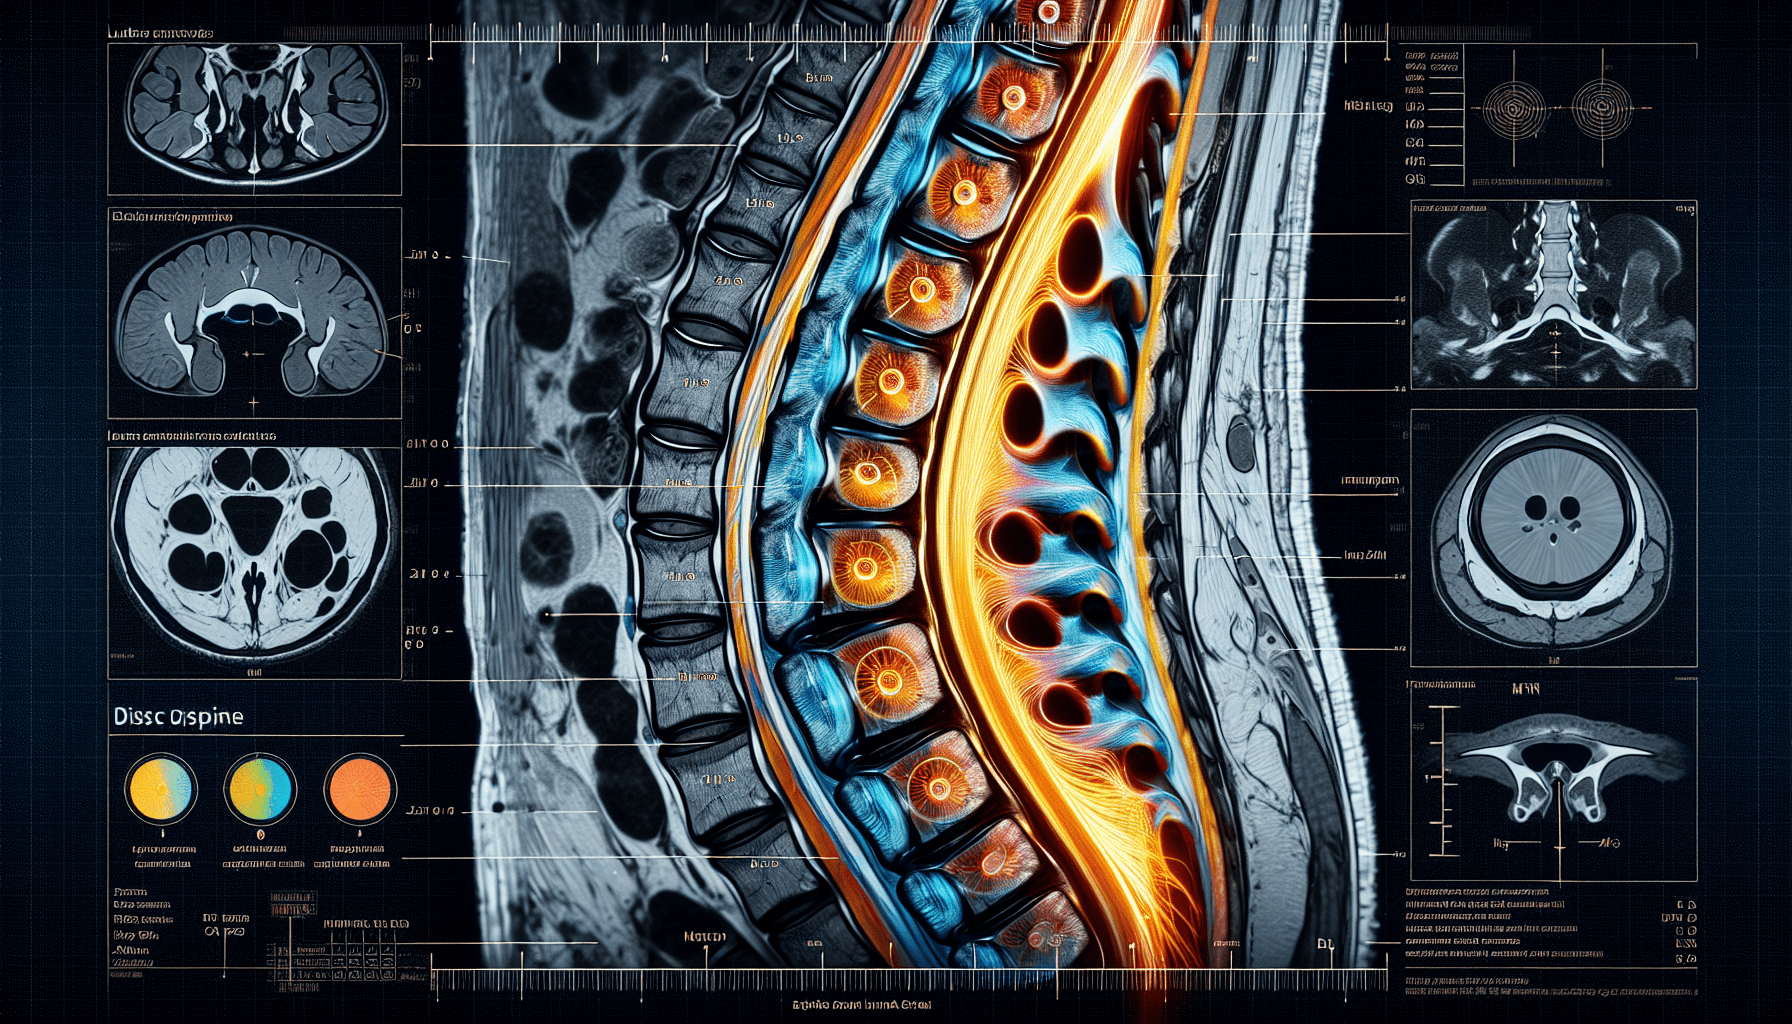

Imaging tests are crucial in diagnosing disc protrusion. Common imaging tests used to diagnose disc protrusion include:

- X-rays: X-rays can help identify any bone spurs, fractures, or misalignments in the spine.

- MRI (Magnetic Resonance Imaging): MRI uses powerful magnets and radio waves to create detailed images of the spine, showing the location and severity of disc protrusion.

- CT (Computed Tomography) Scan: CT scans provide cross-sectional images of the spine, allowing healthcare providers to visualize the disc protrusion from different angles.